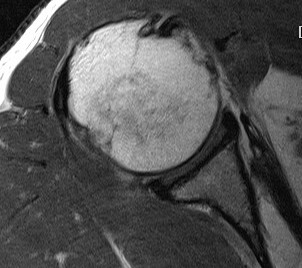

Comma Sign

Comma sign

- medially retracted subscapularis tear

- exposes the superior insertion of superior glenohumeral ligament / coracohumeral ligament

Full thickness retracted subscapularis tear with comma sign

Full thickness completely retracted subscapularis, loss of rotator interval and comma sign

Full thickness completely retracted subscapularis, loss of rotator interval and comma sign